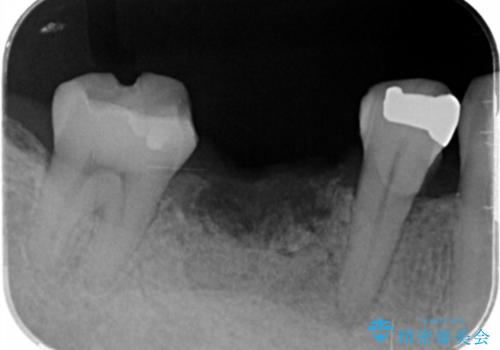

保存できない状態でしたので抜歯をして歯槽堤保存術を行いました。その後大臼歯部にインプラント治療を行いました。

欠損部に1本だけインプラントを埋入しても大きな被せ物になってしまい清掃性が悪くなるので清掃性が良くなるように2本小臼歯用のインプラントを埋入しました。

- 抜歯、歯槽堤保存術・11万円 インプラント体、アバット、仮歯、ジルコニアクラウン・42.9万円×2 骨造成・5.5万円 e-maxインレー・7.7万円 費用は治療当時の料金となります